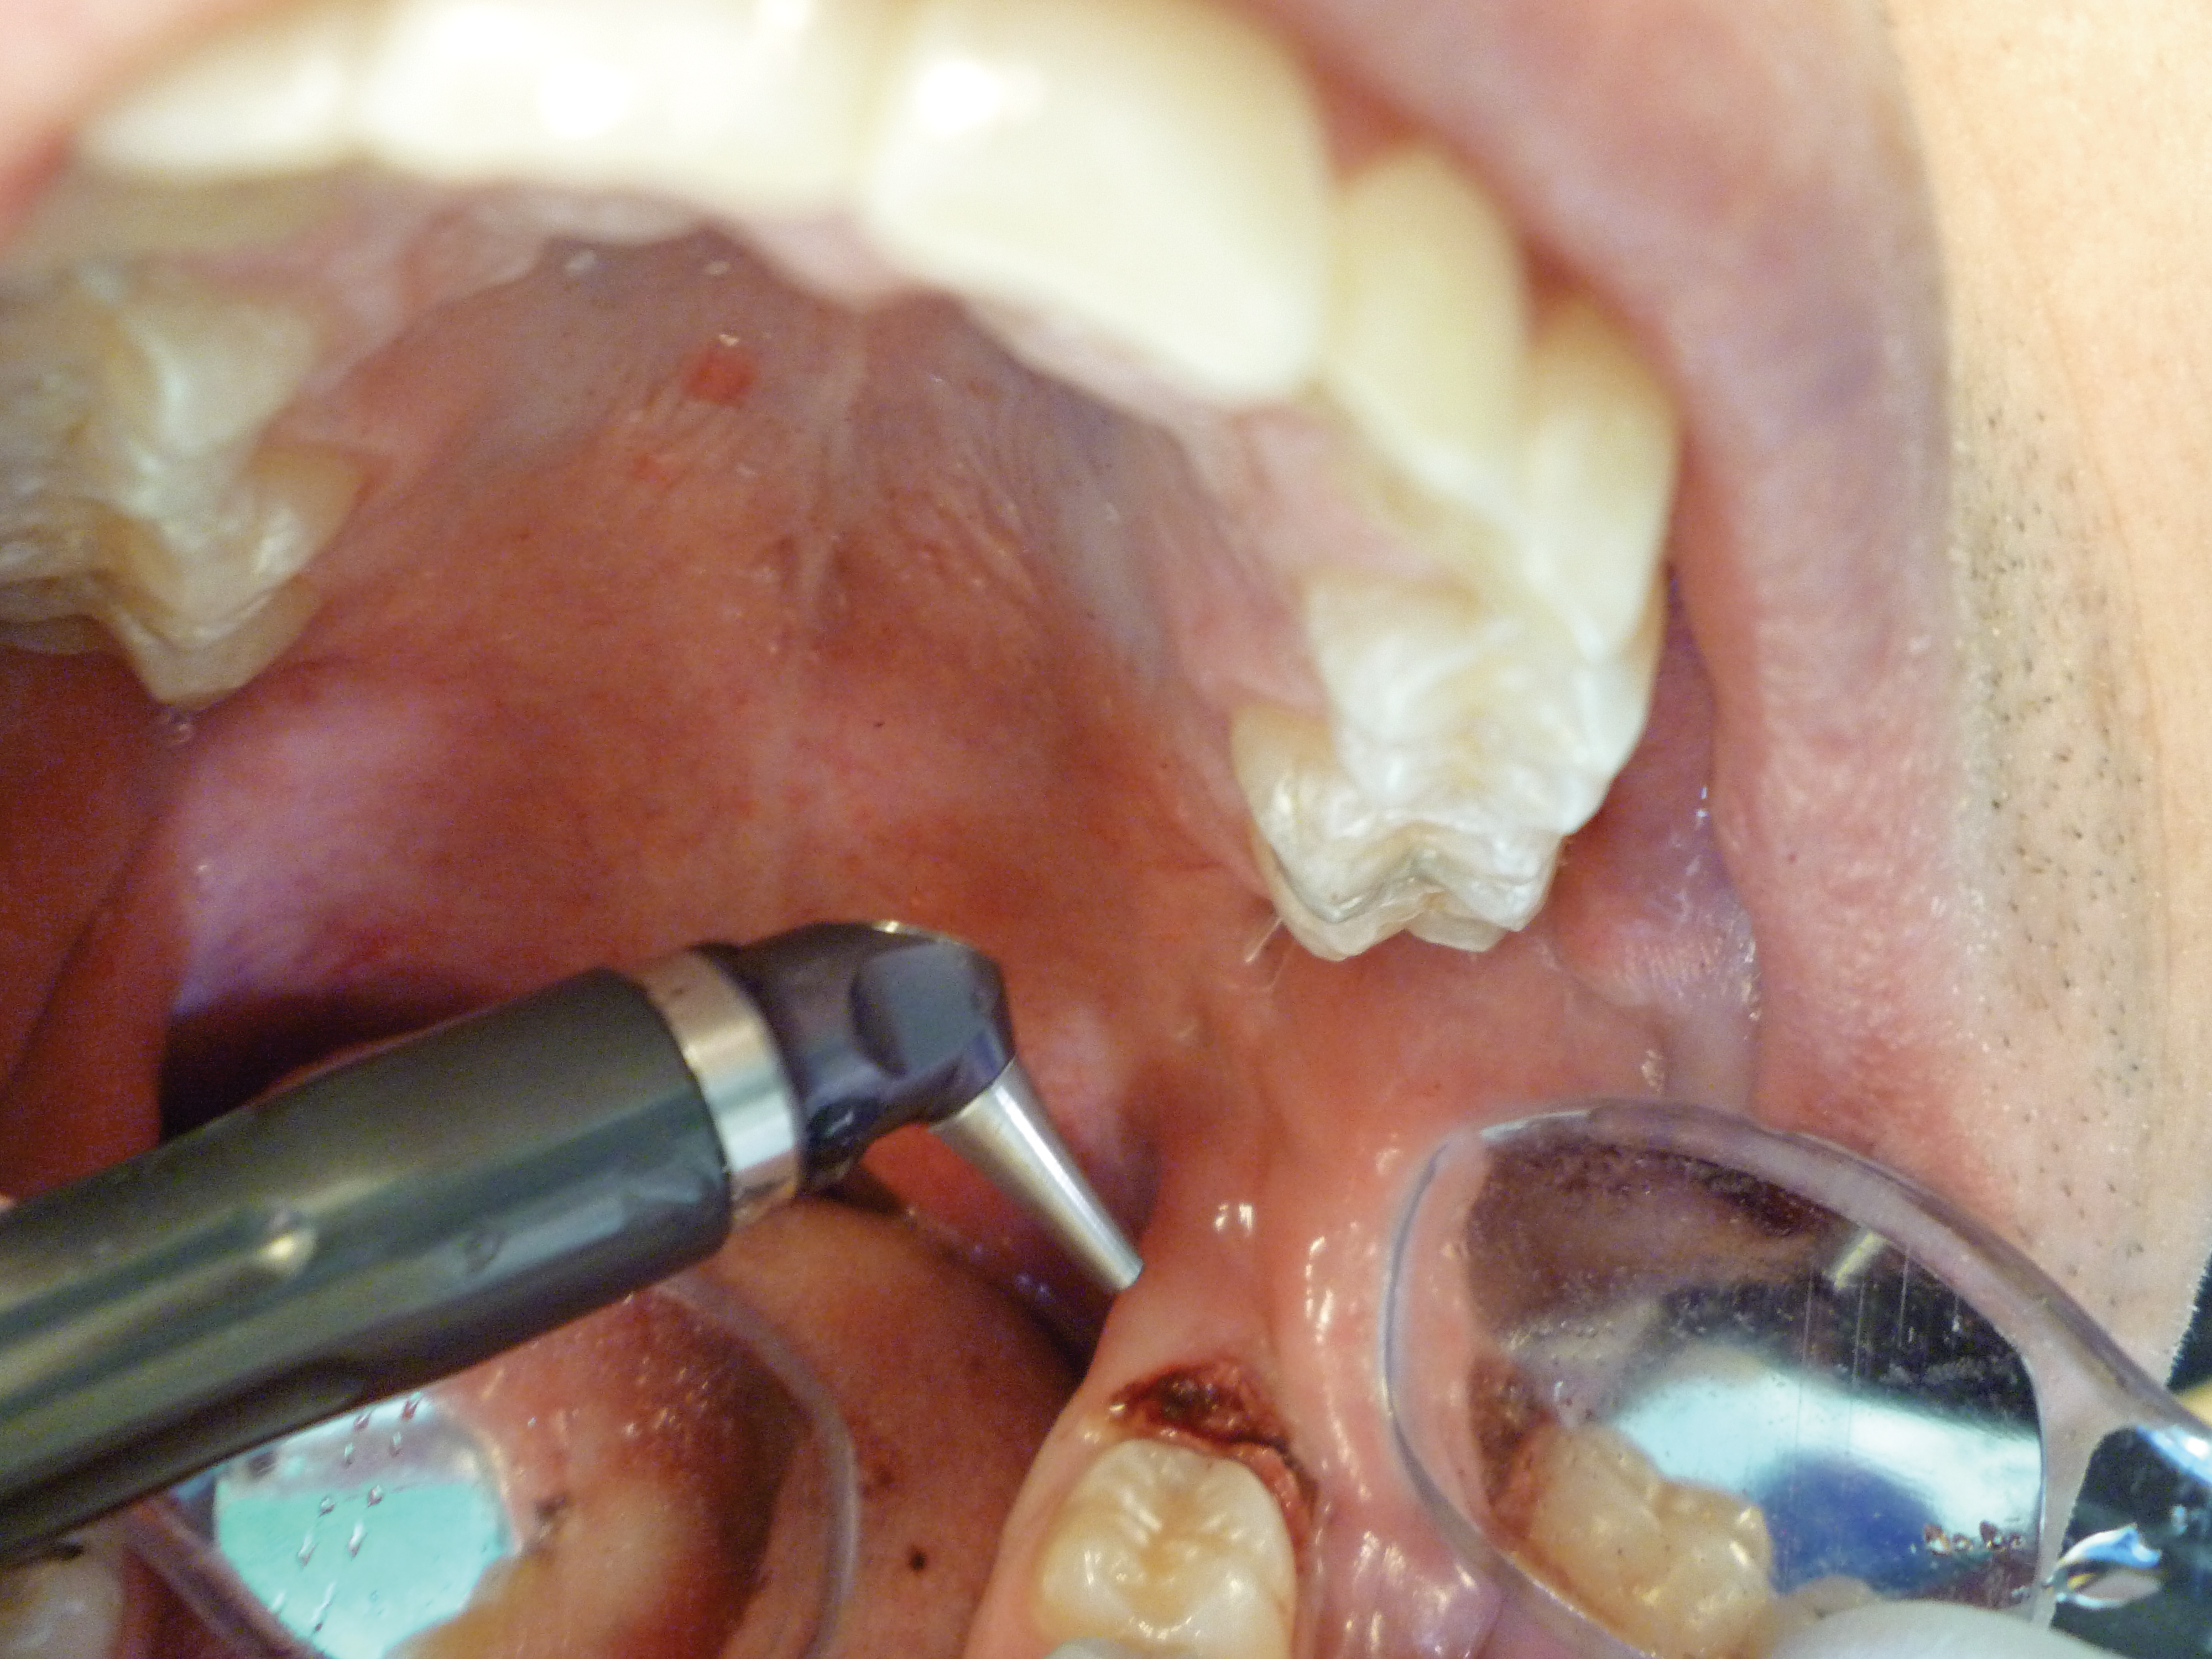

Additional tissue around the primary surgical site was superficially ablated to “feather out” the wound and make the treated area blend with the healthy gingiva better (Figure 7).

Fig 7. Immediate postoperative view. Additional tissue was ablated to make the ablated area blend with the surrounding tissue better. No suturing or dressing was required due to the hemostasis obtained with the CO2 laser.

Figure 7